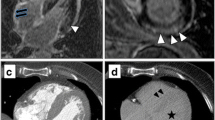

Images were analysed in consensus in a blinded manner on a dedicated platform (ADW 4.6; General Electric, MI, USA) by two readers (V.C. and J.F.D.) with 2 and 15 years of experience in cardiac imaging, respectively. One reader (V.C.) performed the measurements and was approved by the other. IVS thickness was measured on a multi-planar reconstruction performed in the mid-short axis plane of the left ventricle on arterial images. A volume of interest of at least 5 mL was manually defined in the middle part of the IVS from manual contouring of all contiguous axial slices of the arterial data set, and pasted on the unenhanced 5-minute images. Segmentation of unenhanced and 5-minute volumes was manually adjusted if the heart was not exactly at the same position. A volume of interest of at least 5 mL was also defined in the blood pool of the left ventricle on each data set. Mean attenuations (HU) of the IVS and blood pool were noted for each acquisition. The mean MIC (mg/mL) and the mean blood pool iodine concentration (BPIC; mg/mL) were calculated from each data set by using commercially dedicated software (GSI viewer; GE, MI, USA) that extracts iodine concentration (iodine-water as the basic substance; Fig. 1). The iodine concentration ratio was also calculated by dividing MIC by BPIC on arterial (arterial iodine ratio) and 5-minute (5-minute iodine ratio) acquisitions.

Examples of arterial (a, c) and 5-minute (b, d) DECT images obtained in one patient with CA (top row) and one patient with CH (bottom row). Myocardium iodine concentration (MIC) measured on arterial acquisition within the inter-ventricular septum (red line) was in the same range in the CA (2.76 mg/mL) and CH (3.28 mg/mL) patient. The CA patient exhibited a much higher MIC on delayed acquisition (3.44 mg/mL) than the CH patient (1.86 mg/mL). Note the lower contrast between blood pool and myocardium in the CA patient compared to the CH patient on delayed acquisition

On the 5-minute acquisition, MIC was significantly higher (p < 0.001) in CA patients [2.6 (2.3–3.1) mg/mL] than CH [1.7 (1.4–2.2) mg/mL] and control subjects [1.9 (1.7–2.4) mg/mL]. Five-minute iodine ratio was also significantly higher (p < 0.001) in CA patients (0.88 ± 0.12) than CH (0.57 ± 0.07) and control subjects (0.58 ± 0.07). ECV exhibited similar differences: it was significantly higher (p < 0.001) in CA patients (0.56 ± 0.07) than CH (0.36 ± 0.05) and control subjects (0.35 ± 0.04). CH and control patients did not exhibit significant differences for 5-minute MIC, 5-minute iodine ratio and ECV. Five-minute BPIC was in the same range for the three groups. Examples of arterial and 5-minute DECT segmentations on images for a CA and CH patient are reported in Fig. 1.